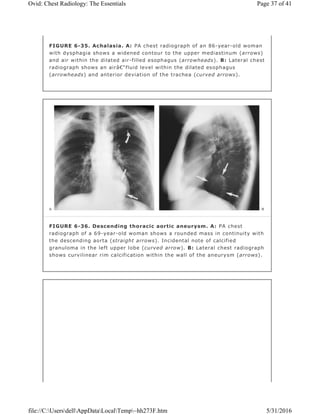

FIGURE 6-35. Achalasia. A: PA chest radiograph of an 86-year-old woman

with dysphagia shows a widened contour to the upper mediastinum (arrows)

and air within the dilated air-filled esophagus (arrowheads). B: Lateral chest

radiograph shows an air–fluid level within the dilated esophagus

(arrowheads) and anterior deviation of the trachea (curved arrows).

FIGURE 6-36. Descending thoracic aortic aneurysm. A: PA chest

radiograph of a 69-year-old woman shows a rounded mass in continuity with

the descending aorta (straight arrows). Incidental note of calcified

granuloma in the left upper lobe (curved arrow). B: Lateral chest radiograph

shows curvilinear rim calcification within the wall of the aneurysm (arrows).